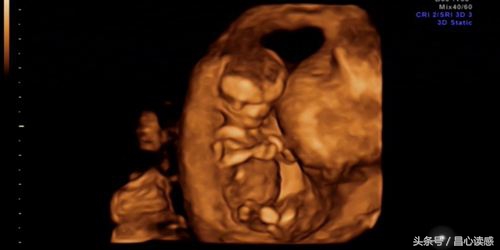

NO.2 子宫胎儿图

达芬奇是最先发现血液的功能,认为血液在人体的新陈代谢当中发挥着重要的作用,并根据自己的见解画下了子宫胎儿图,至今无法解释他是如何划出的。